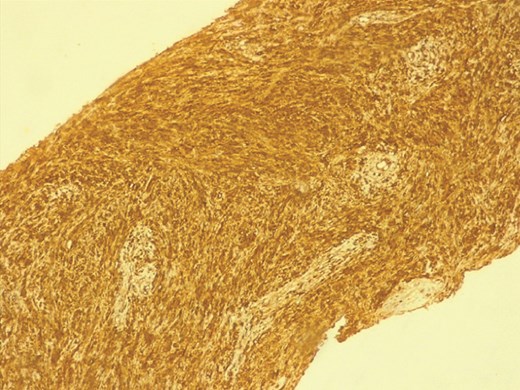

Histopathology demonstrated proliferation of spindle-shaped cells arranged in palisading patterns characteristic of Antoni A regions, intermixed with looser Antoni B areas. The tumor was vascularized by thick-walled, hyalinized vessels, and inflammatory infiltrates were present. These features were highly suggestive of schwannoma. Immunohistochemical analysis revealed strong positivity for S100 protein and smooth muscle actin, while staining negative for desmin and CD34, confirming the diagnosis. The postoperative course was uneventful, and the patient was discharged in stable condition.

Microscopically, the tumor is made out of elongated cells arranged in alignments known as palisades that take one of two patterns: Cells in Antoni type A are displayed in an arranged and firm pattern, while cells in Antoni type B are dispersed loosely within an edematous matrix (Figs 3 and 4). Both of these patterns can coexist and malignant changes are rare [6]. Definite diagnosis is made through histopathological examination and immunohistochemistry [1]. S100 protein positivity and vimentin present hallmark of schwannoma [2].

In our case, histopathological findings showed spindle cell proliferation with Antoni A and Antoni B regions, with the presence of S100 protein and vimentin in the immunohistochemical study.